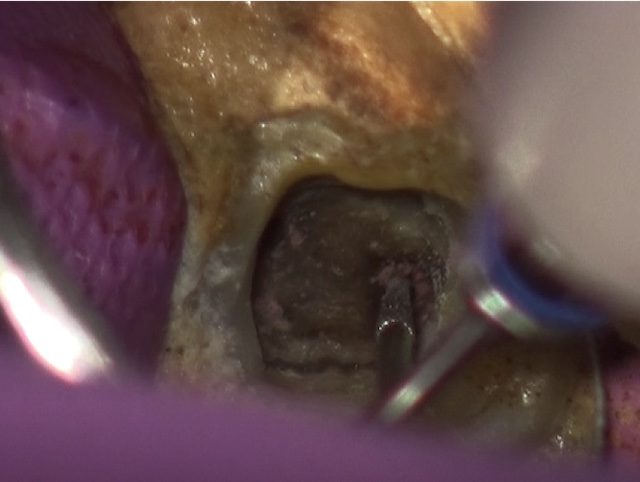

かぶせ物が不適であること(青矢印部)、近心根に根尖病巣があること(青枠部)、根充剤がかなり太いため(赤矢印部)歯質が薄くなっていることなど問題点がいくつかありましたが、他院で治療をしたばかりであり、また上記の条件から再治療には抜歯のリスクが非常に高いことから初診時は患者さんと相談し経過観察することになりました。